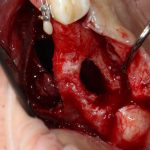

Как на фотографии выше — из-за целого ряда вмешательств и существовавшего ранее ороантрального соустья можно сказать, что от слизистой оболочки верхнечелюстной пазухи почти ничего не осталось. Можем ли мы как-то закончить эту работу? Легко:

Первая операция — мы не можем сразу поставить имплантат из-за почти полного отсутствия кости между полостью рта и дном верхнечелюстной пазухи: